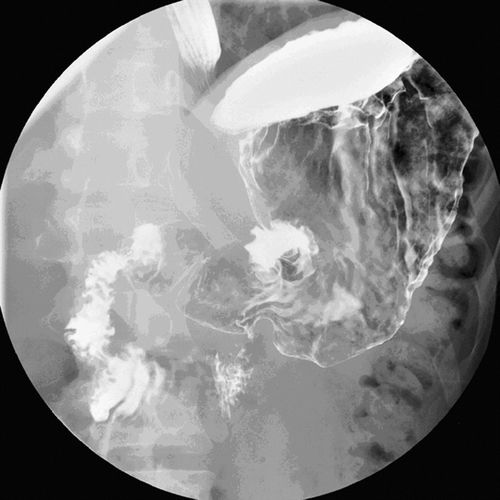

2007年,宾夕法尼亚大学医学院的学者在《美国放射学杂志》上发表了一项研究,去观察那些大胃王比赛冠军以及相关职业选手的胃,在进食后会有怎样的变化。

结果发现这些人群在吃了很多的热狗的情况之下,没有出现急性胃穿孔等大家想象中最危险的场景。在实验过程中,这些大胃王吃了很多的热狗后,胃内并不会快速蠕动,而是逐渐形成一个非常松弛的囊,随后容纳越来越多的食物。

图 | 参考文献